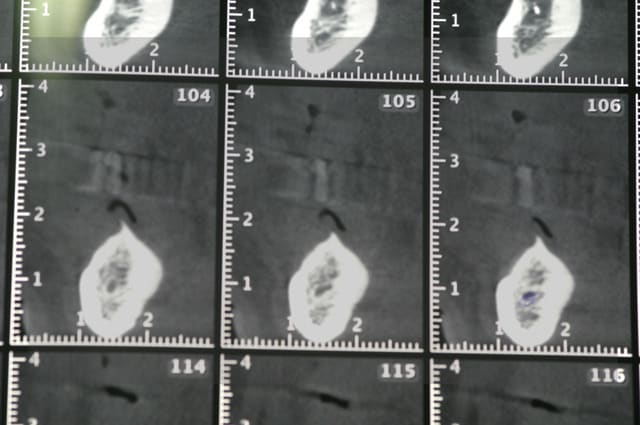

voici quelques images (de mauvaises qualités..désolé) d'un cone beam.

à la base le plan de traitement consistait en la pose de cinq implants et d'un bridge sur pilotis. mais dans le secteur mandibulaire gauche, il me semble que le NDI montre une anatomie un peu bizare. c'est mes yeux ou bien...?